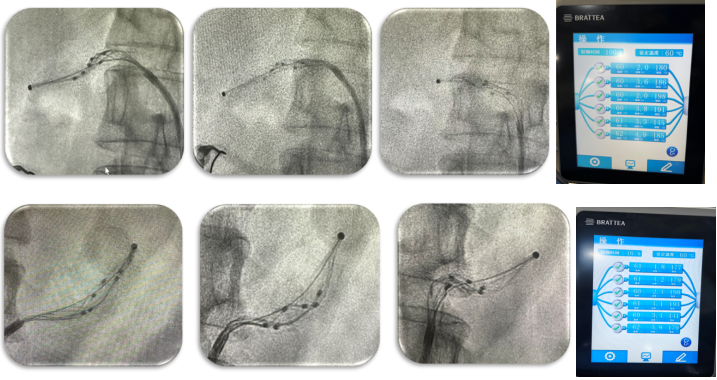

了解清楚肾动脉的情况后,医生拿出特制的“秘密武器”——肾动脉射频消融导管。他们把这个导管慢慢地送到肾动脉主干的远端,就像把一个小工具精准地送到需要“修理”的地方。然后,医生巧妙地控制导管,让导管上的电极紧紧地贴在肾动脉血管壁上,接着以合适的能量进行消融。这个过程就像是给血管交感神经里的“捣乱分子”来一次精准打击,消除引起高血压的“罪魁祸首”。医生在左、右肾动脉主干依次进行了多次这样的消融操作,累计形成了多个有效的消融位点,在肾动脉里布下了一张“降压大网”。

(左右肾动脉手术画面)